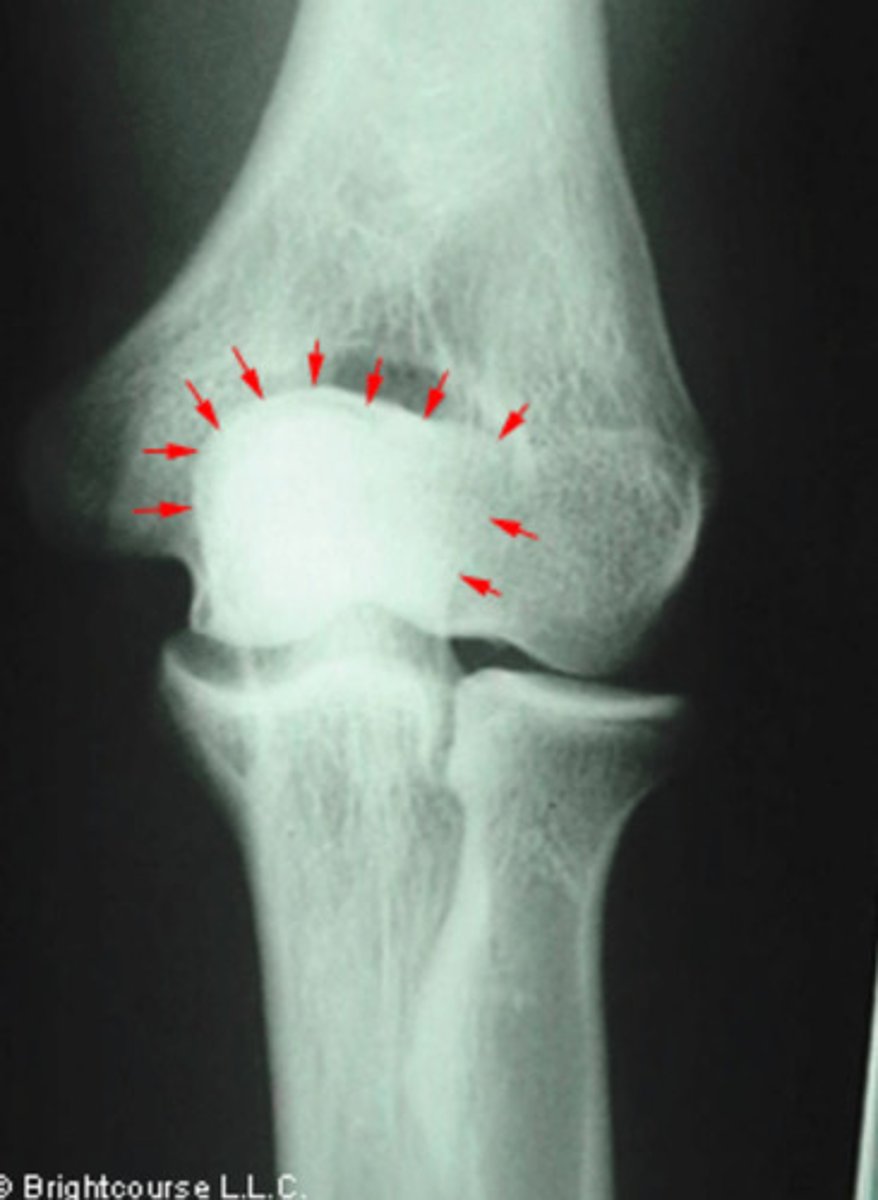

Olecranon fossa

What structure is being pointed out by the arrows?

Capitellum